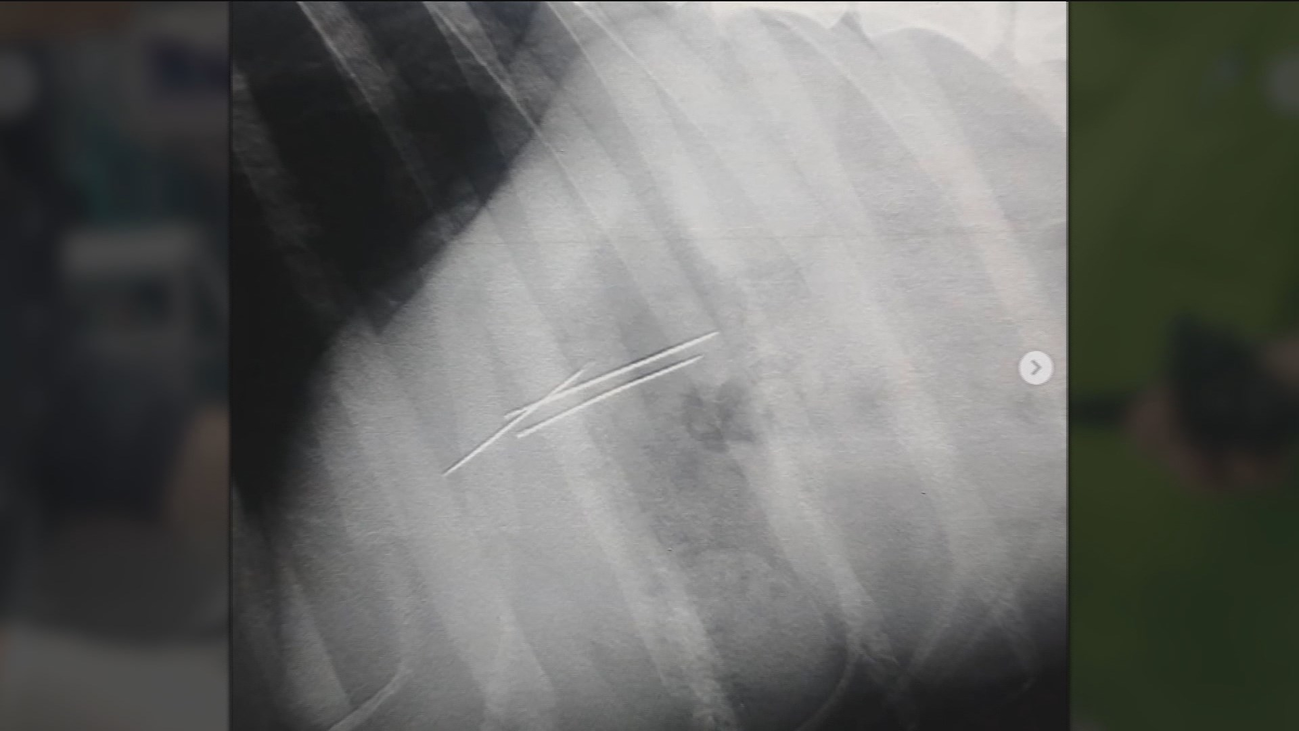

Dos de ellas tuvieron que ser atendidas en el hospital por mordeduras. Fueron trasladadas, en concreto, al Hospital Severo Ochoa.